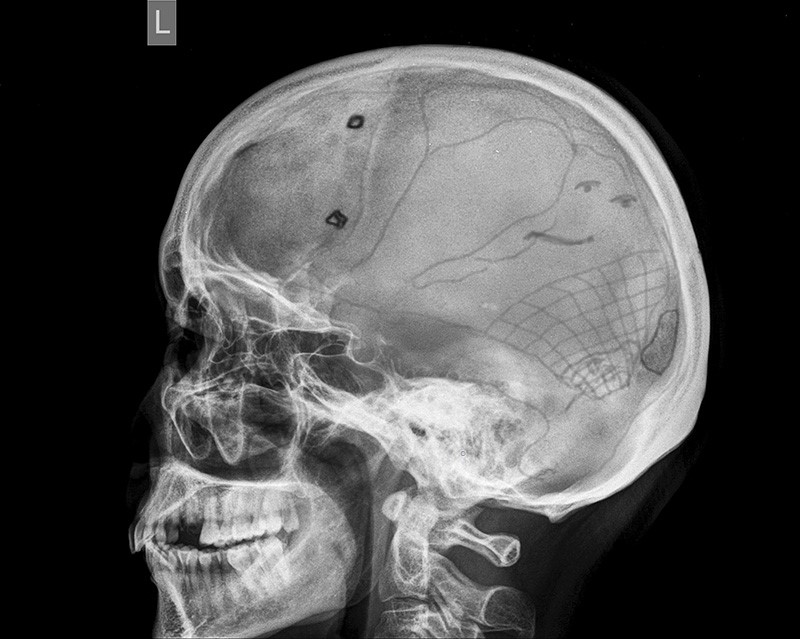

Рентгенография черепа и позвоночника: изображение и диагностика

Раздел: Необычные решения